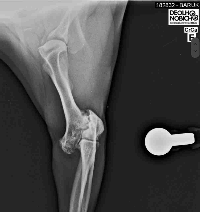

Nosso querido Baruk precisa passar por uma nova cirurgia devido a uma fratura mal calcificada que o levou a se machucar novamente. Infelizmente, dessa vez, a única solução é realizar um procedimento cirúrgico delicado e de alto custo.A cirurgia está marcada para o dia 08/01 e o valor total necessário é de R$8.000,00.Estamos contando com a sua ajuda para devolver ao Baruk a chance de viver sem dor e com qualidade de vida. Qualquer contribuição será imensamente valorizada e fará toda a diferença na recuperação dele.Segue abaixo os orçamento da cirurgia e raio-x da fratura